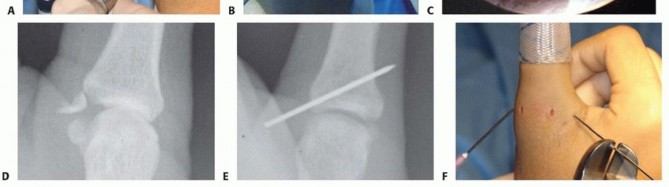

Arthroscopic Treatment of UCL Avulsion Fractures

The arthroscopic approach is exceptionally well-suited for addressing displaced intra-articular avulsion fractures of the UCL base, allowing for precise, visually confirmed reduction without the morbidity of a large arthrotomy.

-

Joint Distension and Portal Establishment:

The procedure begins with accurate palpation of the MCP joint line. Using an 18-gauge needle, we inject 1 to 2 mL of local anesthetic (e.g., 1% lidocaine) directly into the intra-articular space. This distends the tight joint capsule, displacing the neurovascular structures superficially and creating a safe corridor for portal placement.

Our primary viewing portal is the dorsoradial (DR) portal. A small, longitudinal stab incision is made through the skin just radial to the extensor pollicis longus (EPL) tendon at the level of the joint line. Blunt dissection with a mosquito hemostat is used to spread the subcutaneous tissues, protecting the superficial radial nerve branches. A blunt trocar is then introduced, followed by a 1.9-mm, 30-degree arthroscope. This radial vantage point provides an expansive, panoramic view of the ulnar-sided pathology.

Working Portal and Intra-articular Preparation:

Under direct arthroscopic visualization, a spinal needle is utilized to localize the optimal position for the dorsoulnar (DU) working portal. This portal is typically established just dorsal to the adductor pollicis tendon insertion. A longitudinal stab incision is made, and a 2.0-mm or 2.5-mm full-radius shaver is introduced.

The initial step is a meticulous intra-articular debridement. The shaver is used to evacuate the inevitable hemarthrosis and clear away fibrinous debris. A targeted synovectomy is performed along the ulnar gutter to clearly expose the fracture bed on the proximal phalanx and the corresponding avulsed bony fragment attached to the distal UCL.

Fracture Reduction and Percutaneous Fixation:

Once the fracture bed is prepared and cleared of interposed soft tissue, reduction is achieved. This can often be facilitated by applying a varus force to the thumb to relax the UCL, combined with direct manipulation of the fragment using an arthroscopic probe or a small periosteal elevator introduced through the working portal.

While maintaining the reduction under direct arthroscopic visualization, a 0.045-inch Kirschner wire (K-wire) is introduced percutaneously from the ulnar aspect of the thumb, aiming from distal-ulnar to proximal-radial.

The K-wire captures the avulsed fragment and drives it securely into the fracture bed on the proximal phalanx. The anatomical reduction is confirmed both arthroscopically and with orthogonal fluoroscopic views. Depending on the size of the fragment, fixation can be augmented with a second K-wire to prevent rotation, or, if the fragment is sufficiently large, a cannulated headless compression screw can be utilized for definitive, rigid fixation.